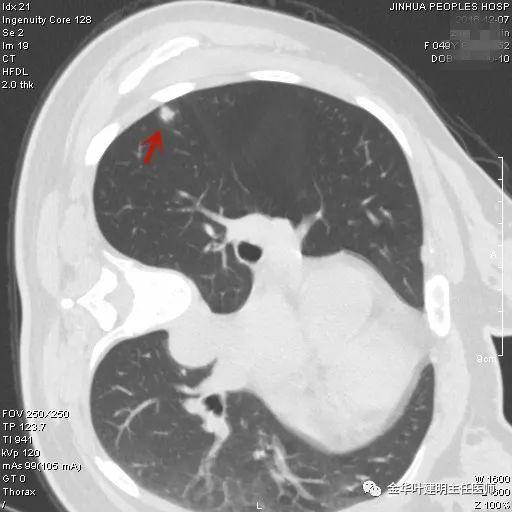

1、以下这种结节是体检发现中最常见的,它们基本上是良性的,可以年度复查:它们都是又上又实的微小结节,直径在5毫米左右或以下。实际上有许多非常焦虑的肺结节病友,他们很多人只是检查发现这种结节。我的建议是:年度复查!若实在不放心,也可半年时复查一次,以确定它不会生长。

叶建明谈结节:检查发现肺实性结节怎么办?个人版实用指南